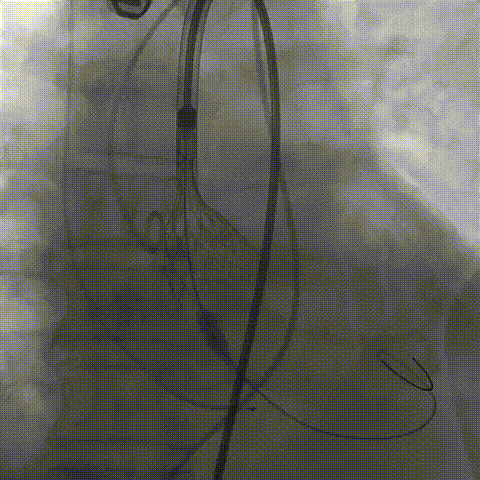

根部造影;直头导丝顺利跨瓣

23mm球囊预扩,冠脉显影正常;输送器顺利过弓

初次释放,无冠窦畸形猪尾难以到达窦底,定位带来挑战;释放至工作位,瓣膜(AV29)位置偏低

瓣膜(AV29)完全回收后重新定位释放

瓣膜(AV29)工作位正交体位造影位置良好,左冠显影正常

瓣膜(AV29)完全脱钩释放后23mm球囊充分后扩,冠脉灌注良好

最后造影